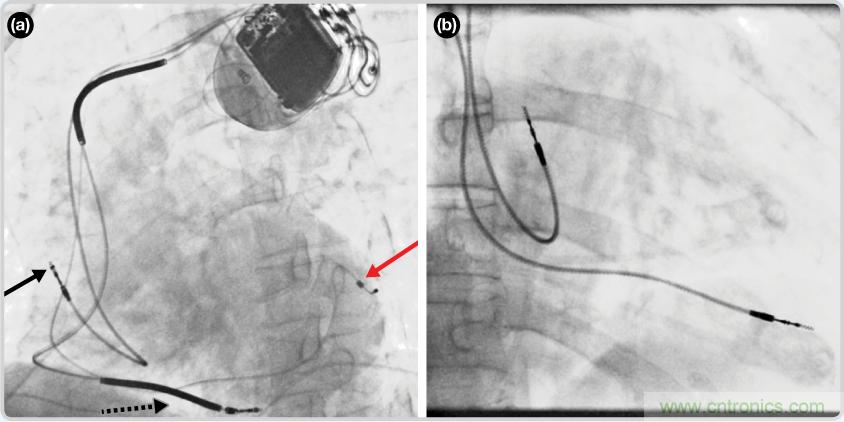

CRT器件在圖4(a)zhongdetoushituxiangzhongkeyikanjian。yishijiushiliyongzhezhongyingxianglaifangzhidaolianxiande。duiyufeizhuanyerenshilaishuo,zhezhongyingxiangshihennanjiedude。keyikandaoxinzangdandandelunkuo——這zhe是shi搏bo動dong中zhong的de心xin髒zang的de靜jing態tai視shi圖tu。起qi搏bo器qi位wei於yu右you心xin房fang上shang,心xin髒zang頂ding點dian指zhi向xiang右you下xia方fang。在zai這zhe個ge典dian型xing的de導dao聯lian線xian放fang置zhi實shi例li中zhong,黑hei色se箭jian頭tou指zhi向xiang右you心xin房fang導dao聯lian線xian。虛xu線xian黑hei色se箭jian頭tou指zhi向xiang右you心xin室shi導dao聯lian線xian。紅hong色se箭jian頭tou標biao示shi的de導dao聯lian線xian隻zhi能neng看kan到dao一yi部bu分fen,這zhe是shi左zuo心xin室shi導dao聯lian線xian(紅箭頭指向電極尖端)。圖4(b)展示的是雙腔起搏器的典型導聯線放置透視圖像。右心房導聯線指向上方,置於右心房中。右心室導聯線則位於右心室頂部。

圖4. 起搏器導聯線放置的透視圖像3 (a). 單腔起搏器;(b).雙腔起搏器